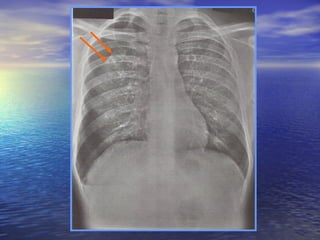

SOFT TISSUES   produce shadow on chest x-ray skin folds produce linear shadows in any direction breast shadow increased opacity over the lower thorax  nipple shadows-round opacity in 4th anterior interspace or lower metallic nipple markers